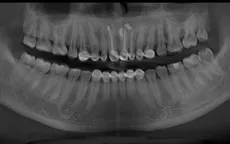

Bóc nang xương hàm gây chảy dịch mũi cho bệnh nhân VTV.vn - Bệnh viện Đa khoa Xuyên Á Long An vừa phẫu thuật cho 2 bệnh nhân bị nang xương hàm trên.

Nang xương hàm do bọc răng thẩm mỹ VTV.vn - Bệnh viện Đa khoa tỉnh Bắc Giang vừa tiếp nhận điều trị cho một bệnh nhân bị nang xương hàm trên.

Bé 12 tuổi phải nhập viện vì biến chứng nang xương hàm VTV.vn - Bệnh viện đa khoa Hùng Vương (Phú Thọ) vừa tiếp nhận điều trị cho một bệnh nhi 12 tuổi bị nang xương hàm.